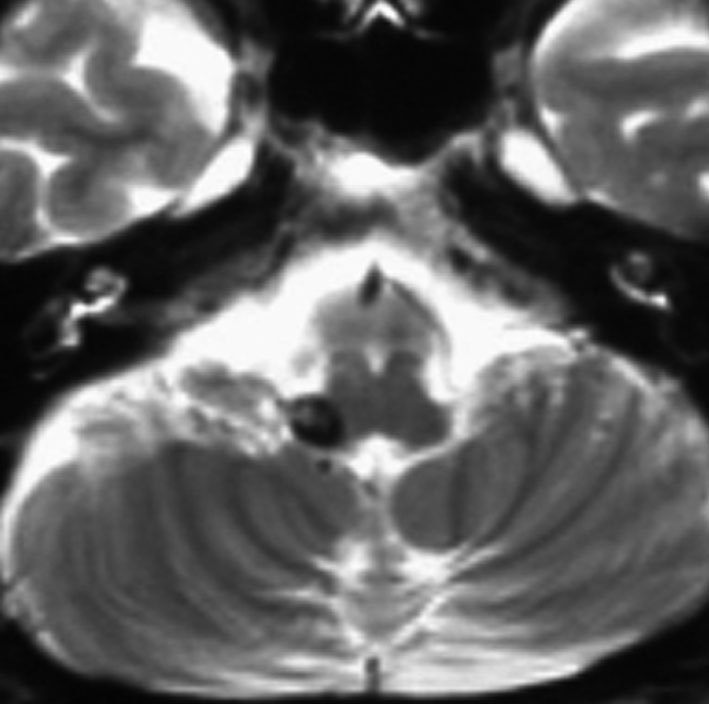

3歳時に28.8グレイの頭蓋照射を受けた子の大脳全般の萎縮性変化です。播種があった例なのでこの放射線治療は救命のためには必要なものでした。